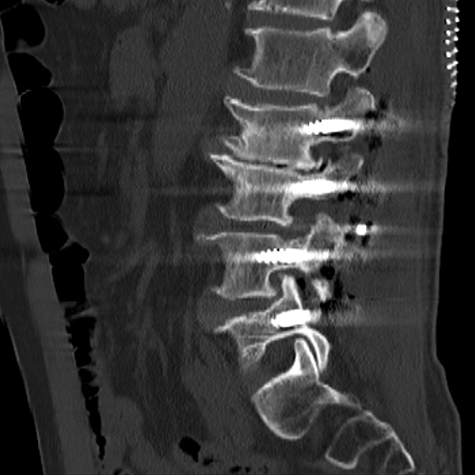

陈勇主任团队顺利为患者置入椎弓根螺钉。术后患者腰腿痛症状较术前明显缓解,肢体活动无障碍,术后3天即在脊柱支具外固定的辅助下下地行走,术后第7天患者恢复情况良好,顺利出院。

▲术中椎弓根螺钉精准置入

▲术后复查X线、CT